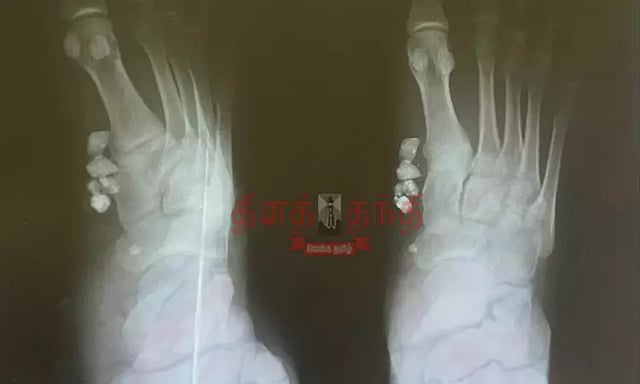

சாலை விபத்தில் காயமடைந்தவருக்கு கணுக்காலில் கற்களுடன் தையல் போட்ட அரசு மருத்துவமனை ஊழியர்கள்...!

அறந்தாங்கி அருகே சாலை விபத்தில் காயமடைந்தவருக்கு அரசு மருத்துவமனையில் தையல் போடப்பட்ட நிலையில் கல் துகள்கள் காலின் உள்ளே இருந்ததால் பரபரப்பு.

இதையடுத்து வீட்டிற்கு வந்த மதிவாணனுக்கு தொடர்ந்து காலில் வலி இந்துள்ளது. இதனையடுத்து அறந்தாங்கியில் உள்ள ஒரு தனியார் மருத்துவமனையில் சிகிச்சை பெற்று எக்ஸ்ரே எடுத்து பார்த்த போது தையல் போட்ட பகுதியின் உள்ளே 3 கல் துகள்கள் இருந்துள்ளது. மதிவாணன் விபத்தில் சிக்கியபோது தரையில் கிடந்த கற்கள் காலின் உள்ளே போயிருந்ததை அறந்தாங்கி அரசு மருத்துவமனையில் சுத்தம் செய்யாமல் தையல் போட்டுள்ளனர்.

இந்நிலையில் இன்று மதிவாணனுக்கு தனியார் மருத்துவமனையில் ஆபரேசன் செய்து கற்களை அகற்றவுள்ளனர்.